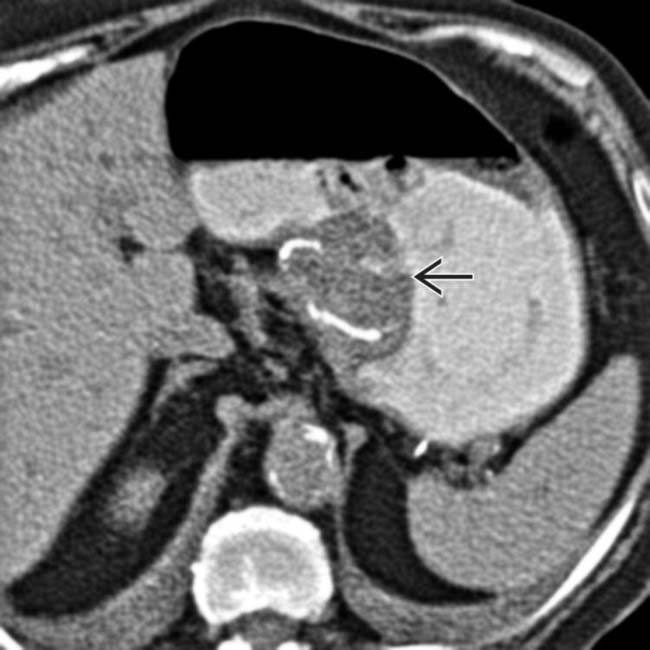

From pubs.rsna.org

Imaging Findings of Successful and Failed Fundoplication RadioGraphics Can You Throw Up After Fundoplication Surgery For myself, it would scare me to think that if i. This can cause nausea (feeling like you’re going to throw up), weakness, cold sweats, cramps, or diarrhea (loose or watery bowel. What happens after a nissen fundoplication? Postoperative dysphagia and dyspeptic symptoms are very frequent and require an integrated approach to determine the best. Immediately after surgery, your throat. Can You Throw Up After Fundoplication Surgery.